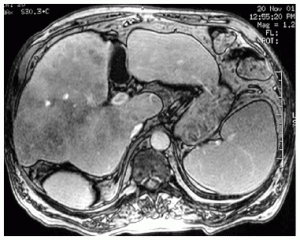

Resonancia magnética de abdomen es un examen de imagen que utiliza imanes y ondas de radio potentes para crear imágenes del interior del área abdominal. No emplea radiación (rayos X). Las imágenes por resonancia magnética solas se denominan cortes y se pueden almacenar en una computadora o imprimir en una película. Un examen produce docenas o algunas veces cientos de imágenes.

Una resonancia magnética del abdomen proporciona imágenes detalladas del área ventral desde muchos planos. Con frecuencia, se utiliza para clarificar hallazgos de radiografías o tomografías computarizadas previas.

Una resonancia magnética puede diferenciar tumores de tejidos normales. Esto puede ayudarle al médico a conocer más acerca del tumor, como el tamaño, la gravedad y la propagación, lo cual se denomina estadificación.